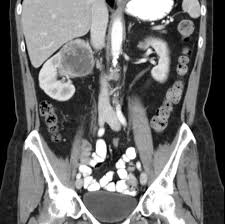

Signs Of Renal Cancer In Males : Kidney Failure Types Symptoms Causes And Treatment : Although it doesn't always draw as much attention as other types of cancer, kidney cancer is one of the 10 most common cancers, especially among people over 55.. Cancer spreads outside the kidney, to multiple lymph nodes or to distant parts of the body, such as the bones, liver or lungs. Signs and symptoms of kidney cancer. The tumor is 7 cm across or smaller and is only in the kidney. Instead, metastatic kidney cancer may cause symptoms in the newly affected areas of the body including: Each year, more than 62,000 americans are diagnosed with kidney cancer.

Symptoms of kidney cancer the most common sign of kidney cancer is blood in the urine (hematuria), which may appear rusty or dark red. People with kidney cancer may experience the following symptoms or signs. Bloody urine is typically the earliest noticeable sign of kidney cancer. The key, as is the … More frequently, the cause is smoking, says dr.

You feel the need to urinate more often. You may also experience difficult or painful urination. In addition, kidney cancer often doesn't show any obvious signs, especially in the early stages. Although it doesn't always draw as much attention as other types of cancer, kidney cancer is one of the 10 most common cancers, especially among people over 55. The risk of kidney cancer increases with age. In men, the development of a varicocele, or a clump of enlarged veins, may appear around a testicle. 97,220 new cases of colon. Dry and itchy skin can be a sign of the mineral and bone disease that often accompanies advanced kidney disease, when the kidneys are no longer able to keep the right balance of minerals and nutrients in your blood. In addition, the spread of kidney cancer to other parts of the body (metastatic disease) gives the first warning signs of the disease (such as a cough or bone pain) in 30 percent of people. Kidney cancer is cancer that begins in the kidneys. And when the gender is taken into account, it is also diagnosed more often in men than women. Instead, metastatic kidney cancer may cause symptoms in the newly affected areas of the body including: Even the slightest amount of blood will affect the color of your urine, giving it either a brown or pink discoloration.

Although it doesn't always draw as much attention as other types of cancer, kidney cancer is one of the 10 most common cancers, especially among people over 55. Blood in the urine (hematuria) low back pain on one side (not caused by injury) a mass (lump) on the side or lower back You may also experience difficult or painful urination. You may also experience difficult or painful urination. Urine may have a pinkish hue or appear dark red.

Plus, many possible kidney cancer symptoms, like blood in the urine, can also result from less. Even the slightest amount of blood will affect the color of your urine, giving it either a brown or pink discoloration. Breast lumps are relatively reliable. Tests and procedures used to diagnose kidney cancer include: It is important to note that the signs of kidney cancer are shared by many other benign (noncancerous) conditions. It is more common in men than in women. Dry and itchy skin can be a sign of the mineral and bone disease that often accompanies advanced kidney disease, when the kidneys are no longer able to keep the right balance of minerals and nutrients in your blood. Today, the most common symptoms of kidney cancer are anemia, fatigue, weight loss, loss of appetite, and a fever. In 2019, about 73,820 new cases of kidney cancer will occur. Feeling a mass on your abdomen, side, or lower back. As a rule it is painless. In addition, kidney cancer often doesn't show any obvious signs, especially in the early stages. Cancer spreads outside the kidney, to multiple lymph nodes or to distant parts of the body, such as the bones, liver or lungs.

Most symptoms have to do with your kidney function and tumor growth. Some possible signs and symptoms of kidney cancer include: There may be enough blood to change the color of the urine to orange, pink, or, less often, dark red. In addition, the spread of kidney cancer to other parts of the body (metastatic disease) gives the first warning signs of the disease (such as a cough or bone pain) in 30 percent of people. Lungs, causing cough and shortness of breath bones, resulting in bone pain or fracture brain, presenting as headaches, confusion or seizures